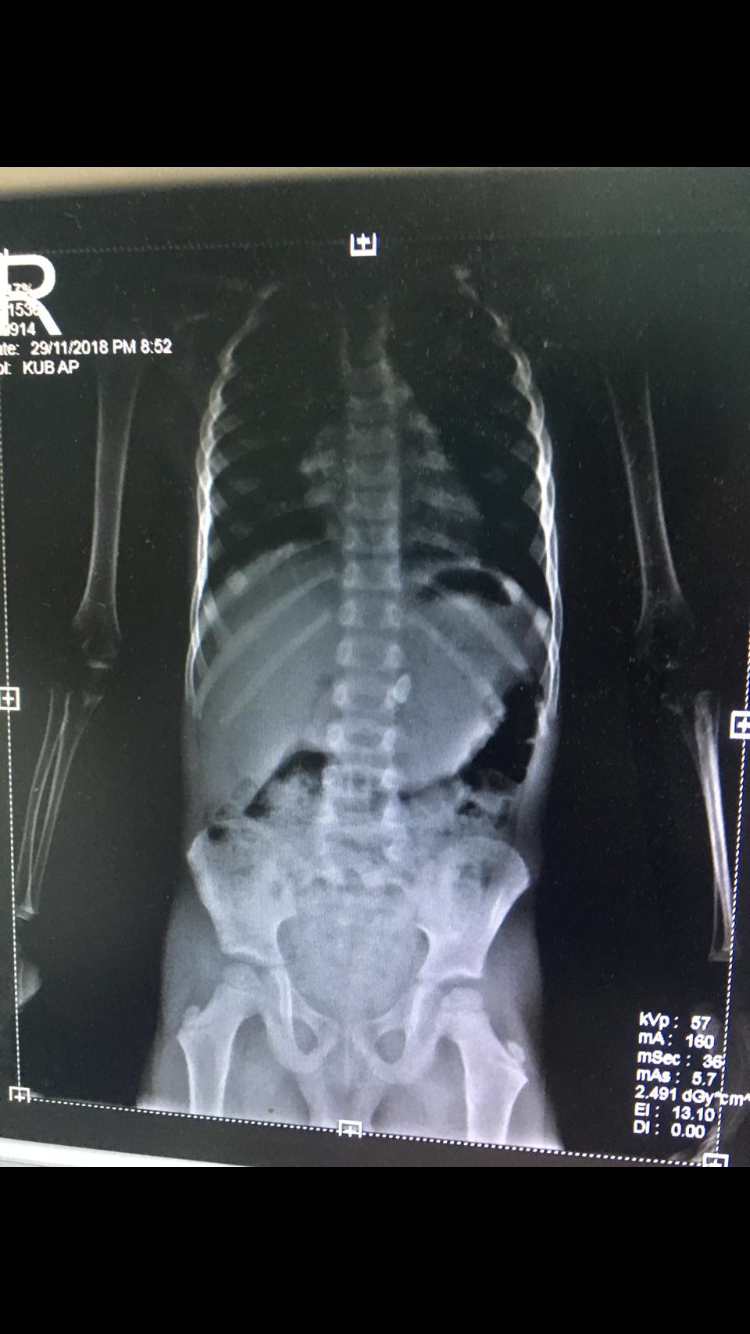

يابنات عندي صوره الاشعه لولدي واضح ان الحديده موجوده

وفي المستشفى يقولون هذي فقره متحركه من العمود الفقري

راسلنا دكتور اطفال وقال ان القطعه الحديديه موجوده ببطنه وحط عليها علامه

هذي الصوره يابنات

هذي العلامه اللي حطها الدكتور وقال هذي القطعه هذي صوره الاشعه في المستشفى اللي يقولون فقره!!

السلام عليكم كيفكم حبايبي جميعاً اسفه مادخلت وطمنتكم يابنات عندي صوره الاشعه لولدي واضح ان الحديده موجوده وفي المستشفى يقولون هذي فقره متحركه من العمود الفقري راسلنا دكتور اطفال وقال ان القطعه الحديديه موجوده ببطنه وحط عليها علامه وقال نراقبه مع البراز الله يكرمكم عشان ممكن تخرج ولو صار امساك او الم بالبطن او قيء نوديه المستشفى فوراً وانا للحين انتظره تطلع 😢 هذي الصوره يابنات هذي العلامه اللي حطها الدكتور وقال هذي القطعه هذي صوره الاشعه في المستشفى اللي يقولون فقره!!